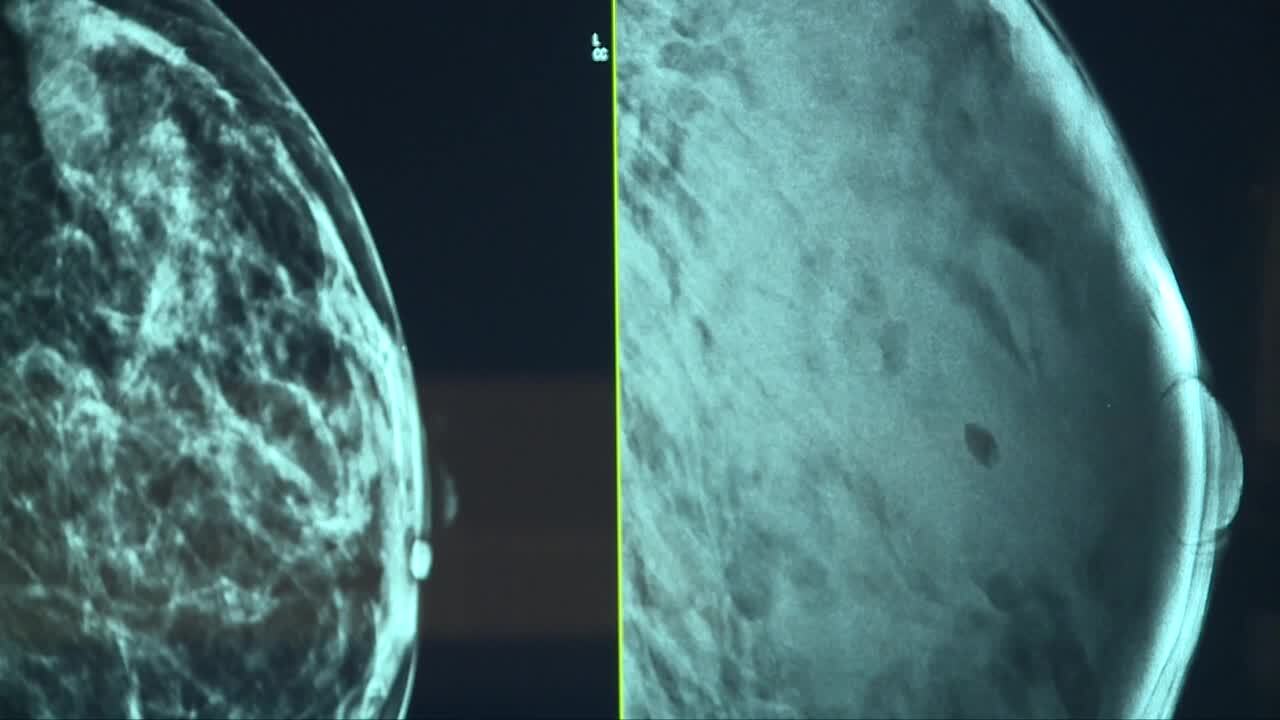

With dense breasts, it's easy for tumors to hide when doctors are looking at mammograms and X-rays.

“That tissue is white on X-ray. The problem with that is it can hide small lumps or masses because those lumps and masses are the same shade of white,” Dr. Shah explained.

If a patient has dense breasts a mammogram — preferably a 3D mammogram — and additional screenings like an ultrasound or MRI would be needed.